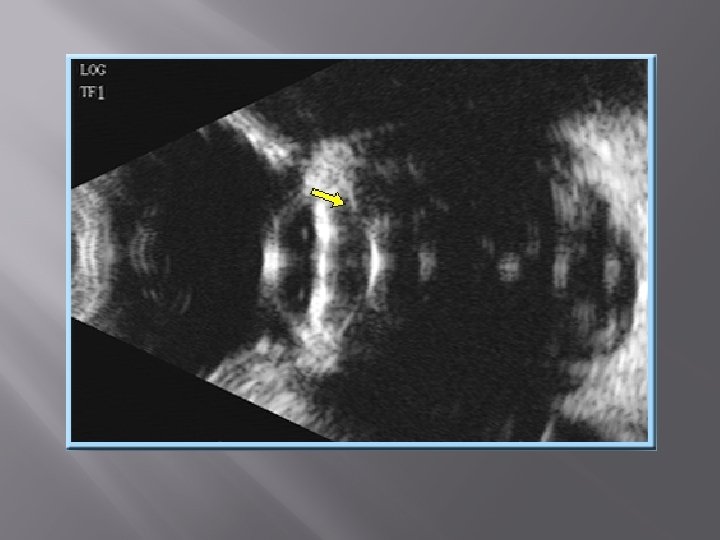

NORMAL ANATOMY ON B-SCAN � � � � Normal anatomy is obtained by placing the probe on cornea such that the marker faces temporally. First structure to be visualised is the posterior capsule which is seen as a curvilinear echogenic structure. Vitreous cavity is circular in shape and is anechoic. Optic disc is small area at the anterior end of optic nerve. Macular region is temporal to the optic disc. Optic nerve is seen as an anechoic linear shadow in the retro-ocular space. Orbital fat is seen as a triangular echogenic structure. Extra ocular muscles are seen as linear hypo echoic structures at the periphery of the orbital fat.

The most important role of B scan ultra sonography is to localise the lesion to eye or orbit by using various scan planes. This is called as topographic ultrasonography. The image shows elevated lesion in macula obtained by placing the probe over cornea with marker facing temporally.